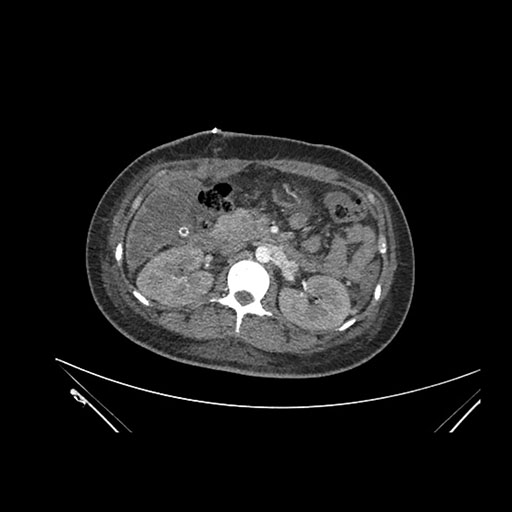

Axial Arterial

Axial Venous

Imaging analysis

Based on initial findings, which issue(s) would you be most concerned about?